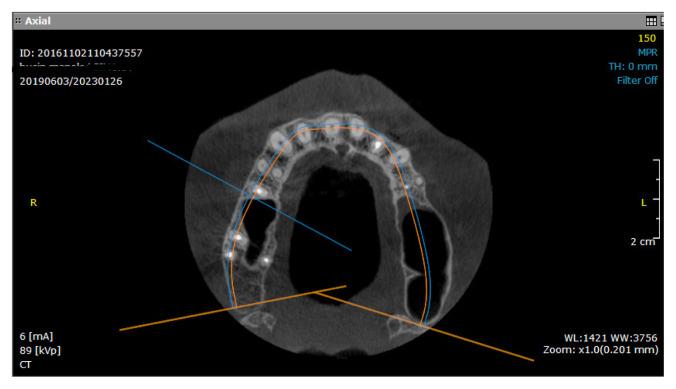

Much of the research published involves using artificial products, like xenografts and resorbable collagen membranes, after a prior Cone Beam Computer Tomography (CBCT) investigation. Nowadays, more accessible access, less financial costs, a biological approach, and faster healing are objectives that surround this procedure. Leucocytes and platelets rich in Fibrin (L-PRF) are a natural component with a high concentration of growth factors. Due to its regenerative properties and lack of complications, it is used in several medical fields, like orthopedics, dermatology, and oral surgery. This retrospective study aims to compare results in bone height and volume obtained through external sinus lift, either by using xenografts or autologous plasma rich in fibrin, by evaluating the quantity of new bone formation from a radiological point of view.

Fifty-eight Caucasian patients were included in this retrospective study; 48 were submitted to xenograft procedure, and 10 were selected for L-PRF grafting material with simultaneous implant placement. Lack of clinical and histological studies performed on patients with L-PRF surgeries limited us in choosing a larger group for the radiological analysis. CBCT evaluation was performed before surgery and 6 months after. All patients selected for the study presented good general and oral health, acute oral and sinus infections excluded; smoking and periodontal disease were also criteria of exclusion. Two operators performed the measurements in pre-established landmarks in different time frames. The two independent groups were compared with the Wilcoxon rank-sum test for quantitative data. Qualitative characteristics were described as counts and percentages. All analyses were performed in an R environment for statistical computing and graphics.